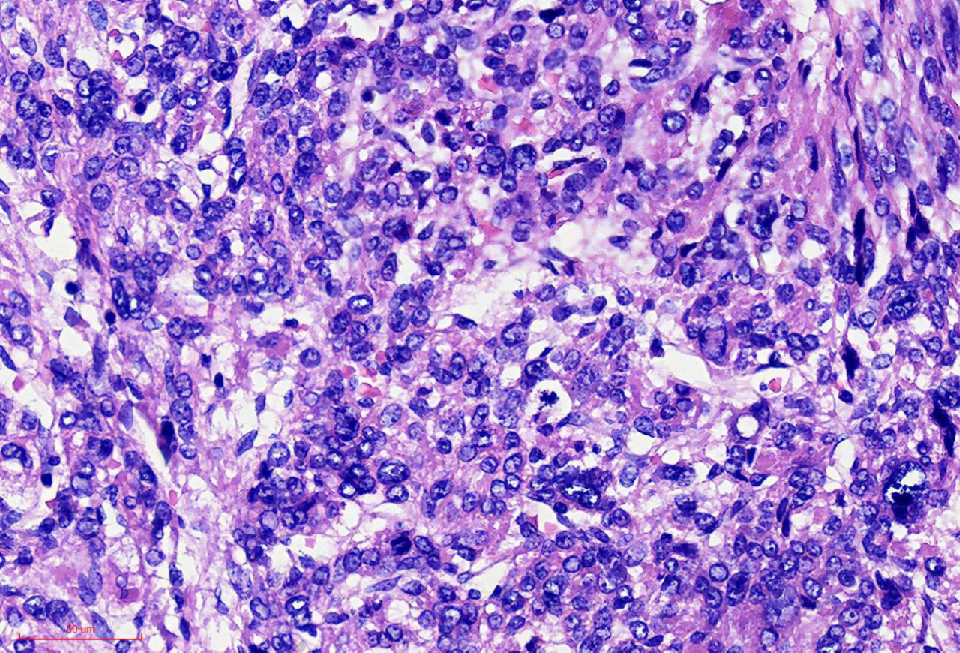

组织学改变

肿瘤细胞丰富

瘤细胞排列呈血管外皮瘤样

瘤细胞疏密相间

异型明显,可见核内包涵体,红核仁

未见凝固性坏死

核分裂象数2个/10HPF

细胞丰富

鹿角样/血管外皮瘤样血管

肺水肿样水肿/疏密相间

细胞核奇异,嗜酸性胞质,有显著的嗜酸性核仁,核仁周围可见空晕,部分细胞呈横纹肌样

核分裂象少见

无凝固性坏死